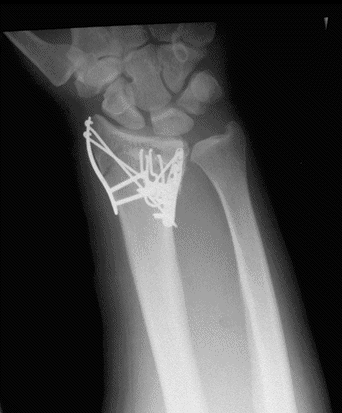

Case3 Postop